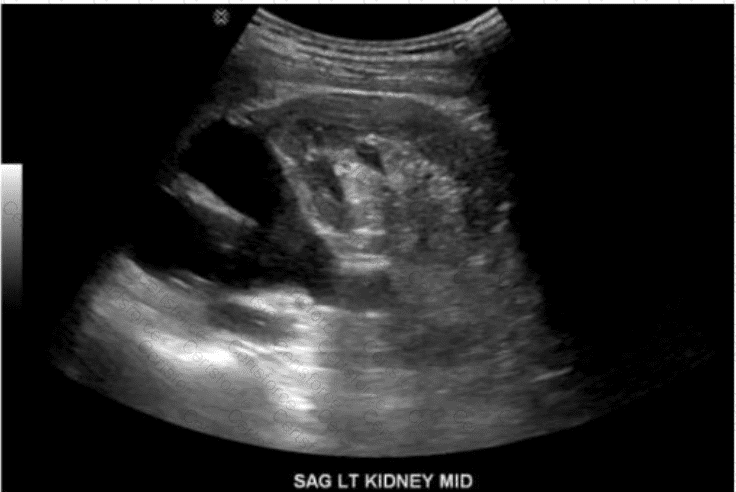

The ultrasound image labeled “SAG LT KIDNEY MID” demonstrates a left kidney with two separate, centrally located echogenic renal sinuses separated by intervening renal parenchyma. This appearance is classic for a duplicated collecting system.

A duplicated collecting system (also known as duplex kidney) is a congenital anomaly in which a single kidney contains two separate pelvicalyceal systems. It may be complete (with two ureters) or incomplete (partial duplication of ureters). This condition is one of the most common congenital anomalies of the urinary tract.

Two separate central echogenic renal sinus regions seen within one kidney

Intervening parenchyma between the two sinuses

May show associated findings: hydroureteronephrosis (especially of upper pole moiety), ureterocele

Best visualized in sagittal plane